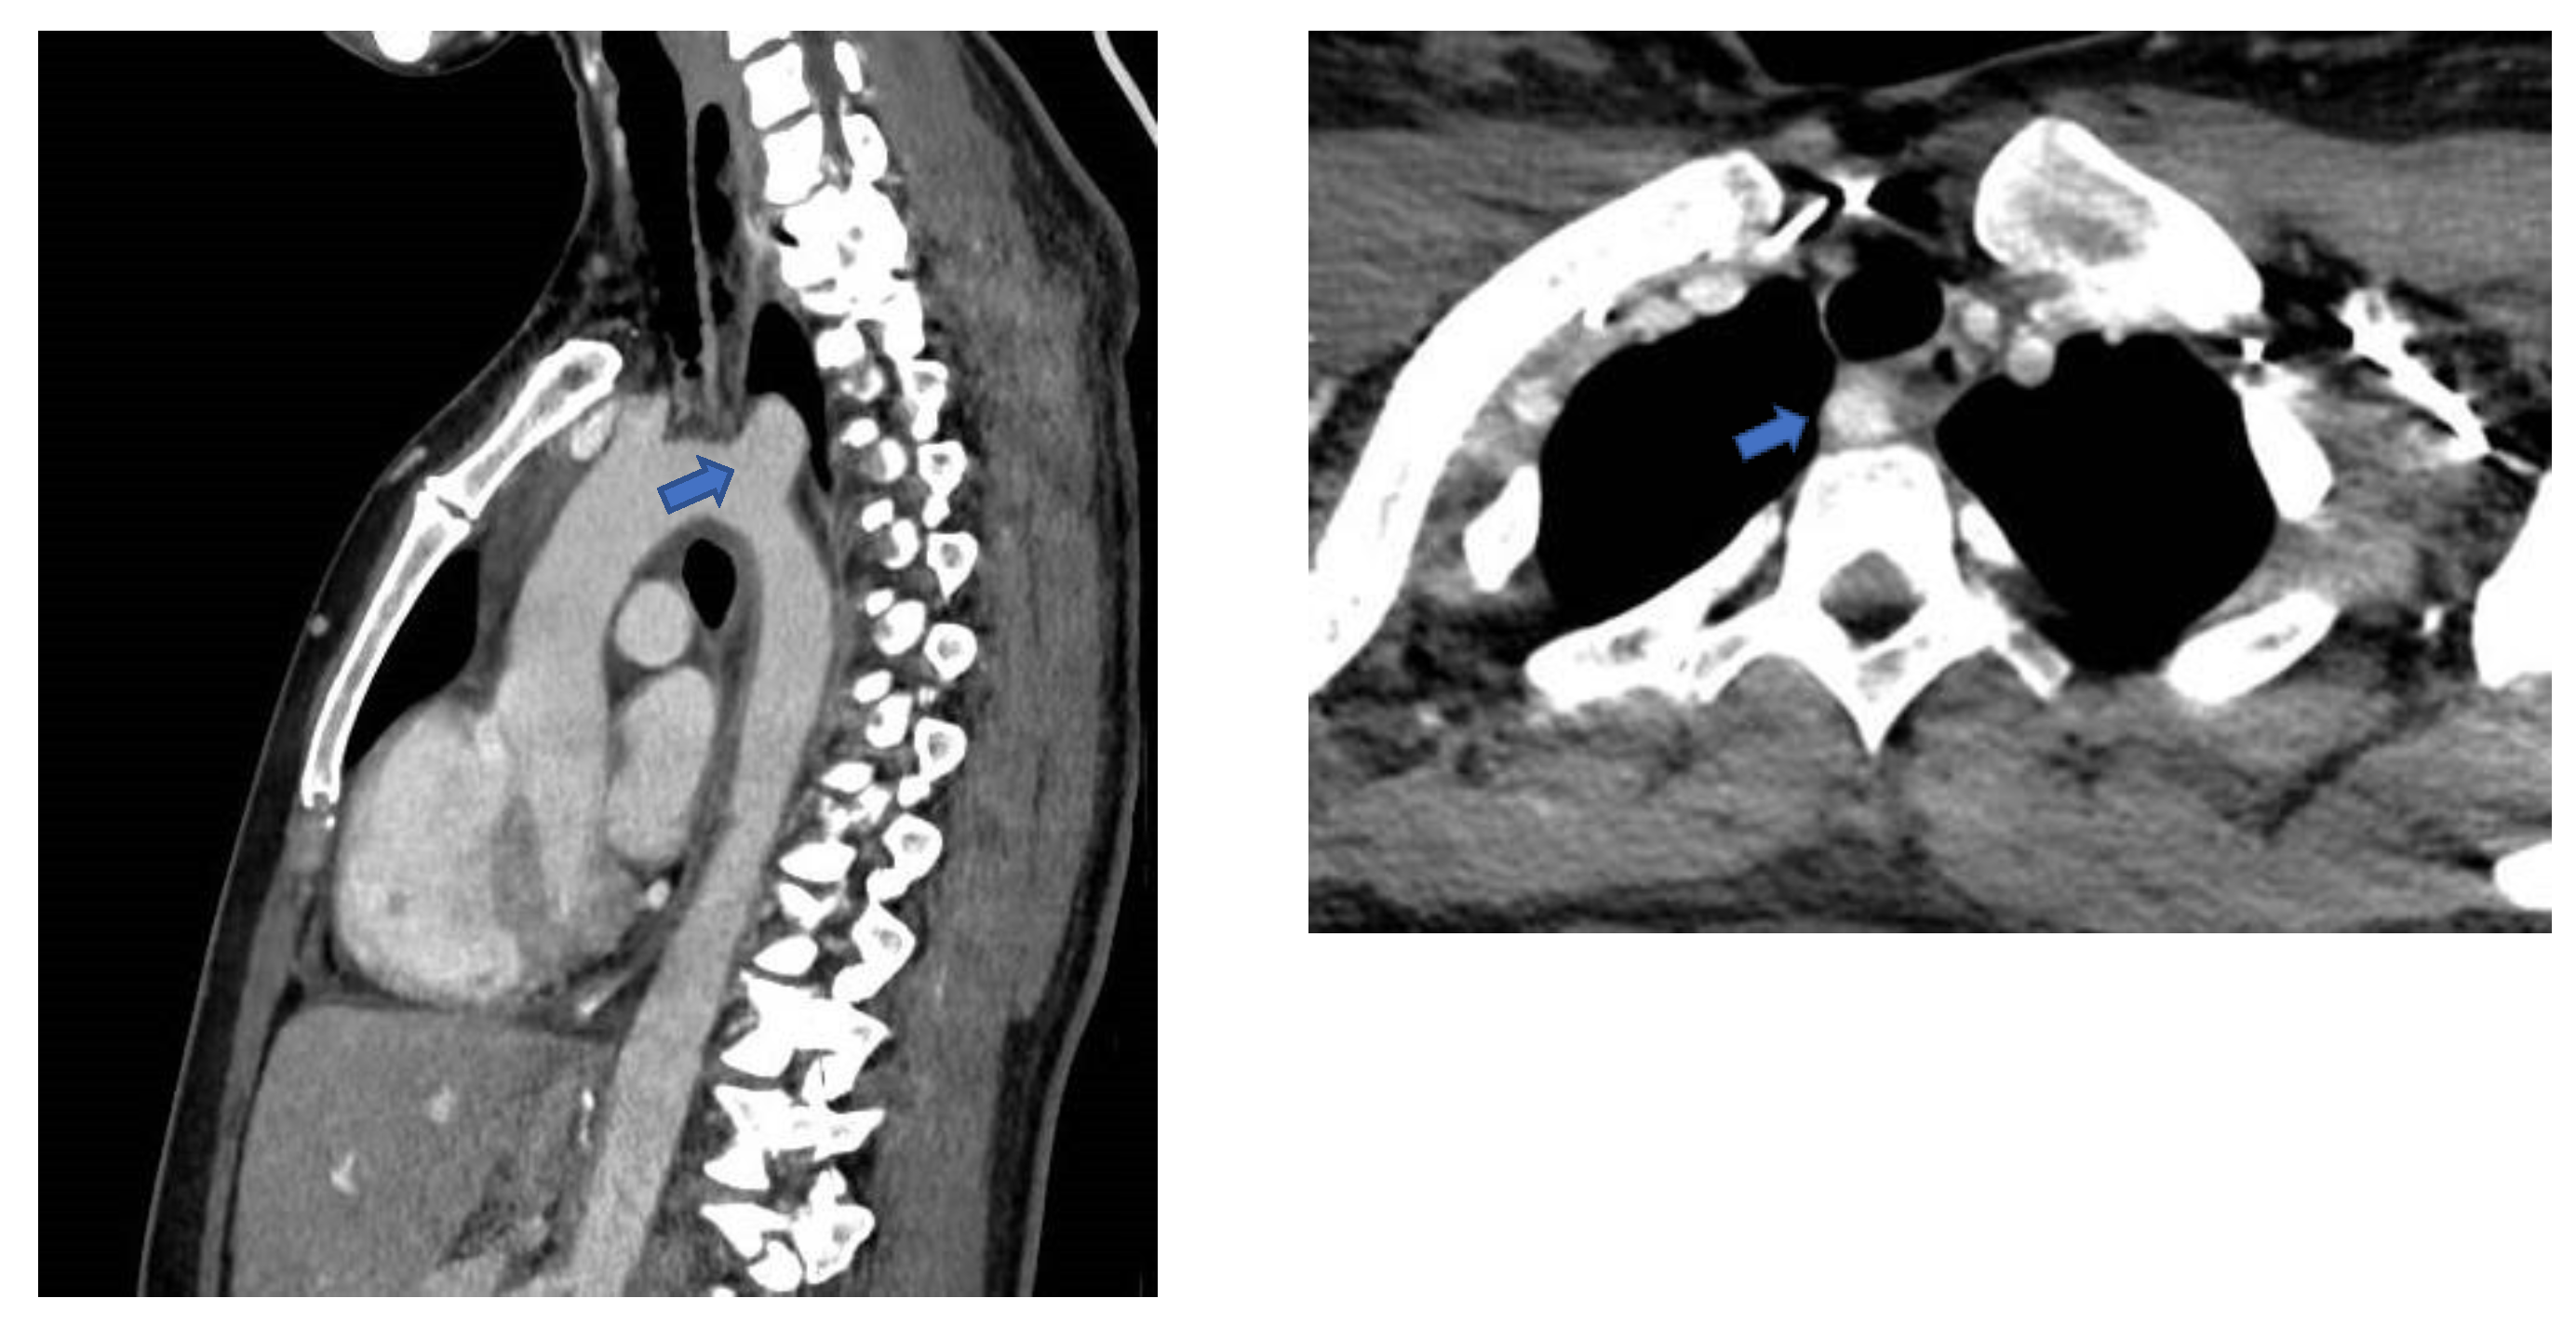

A 44-year-old patient underwent gastric bypass surgery in 2015, resulting in a remarkable weight loss of 30 kilograms. The patient presented with a progressively worsening dysphagia over the past six months. Diagnostic investigations revealed a pulsatile compression of the esophagus, suggestive of dysphagia lusoria. Subsequent computed tomography (CT) imaging confirmed the presence of an arteria lusoria, accompanied by a Kommerell's diverticulum provided (Figure 1). Given the symptomatic nature of the condition and the concurrent presence of Kommerell's diverticulum, surgical intervention was deemed necessary.

Figure 1. Sagittal and transversal CT scan views revealing an aberrant origin of the right subclavian artery from the aortic arch and a dilated appearance of its proximal segment, with a retro-esophageal course.